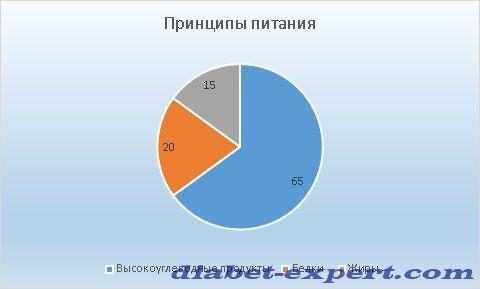

Питание при диабете 1 типа

Основные принципы питания в % соотношении белков, углеводов и жиров представлены на диаграмме.

Обратите внимание! Желательно включить в меню продукты, которые быстро всасываются кишечником. Предпочтение следует отдать сложным углеводам и веществам с высоким содержанием клетчатки и клейковины.